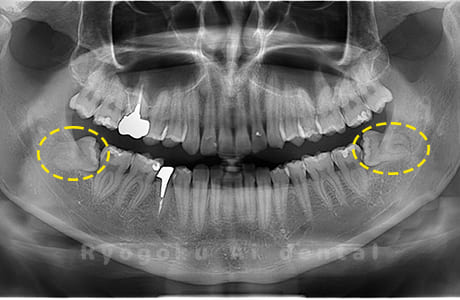

Case01

- 原因

- 水平埋伏智歯

- 治療内容

- 下顎の水平埋伏智歯を抜歯

<リスク・副作用>

手術後は痛み、腫れ、痺れなどの副作用が生じる場合があります。